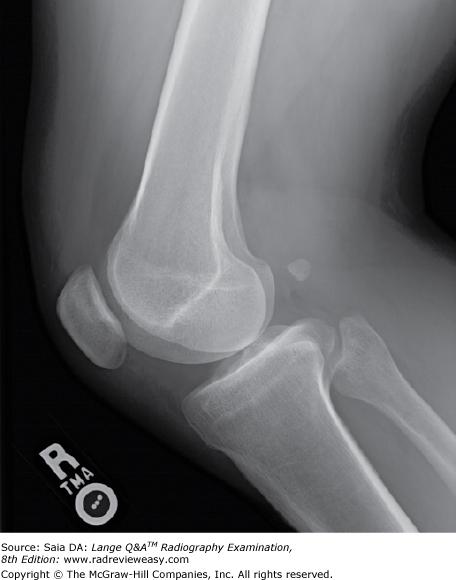

Which of the following projections of the elbow should demonstrate the radial head free of ulnar superimposition?

A AP B Lateral C Medial oblique D Lateral oblique

Lateral oblique

Which of the following projections of the elbow should demonstrate the coronoid process free of superimposition and the olecranon process within the olecranon fossa?

Medial oblique

The AP oblique projection (medial rotation) of the elbow demonstrates

which of the following?

1. Radial head free of superimposition

2. Olecranon process within the olecranon fossa

3. Coronoid process free of superimposition

2 and 3 only

An AP oblique (lateral rotation) of the elbow demonstrates which of the following?

- Radial head free of superimposition

- Capitulum of the humerus

- Olecranon process within the olecranon fossa

1 and 2 only